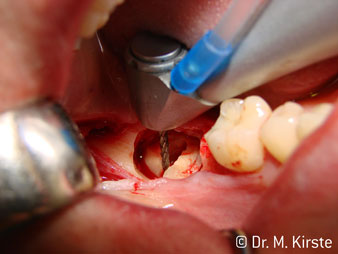

Die Winkelwahl des 45° Handstücks bringt viele Vorteile in der Anwendung. Chirurgisch tätige Kollegen, und für diese ist das Handstück in erster Linie entwickelt worden, werden schnell bemerken, dass man sehr gezielt arbeiten kann. Insbesondere bei der Weisheitszahnentfernung (Abb. 2) bedarf es keiner großen Weichteilabspreizungen im Wangenbereich (Abb. 3). Die Handstückkopfgestaltung kombiniert mit leichten Kopfdrehungen bei der Präparation lassen ein sicheres und schnelles Arbeiten im retromolaren Bereich zu.

Die professionelle Lagergestaltung im Innenleben des Handstückkopfes garantiert einen ruhigen Lauf der Bohrer, bei der Zahn- oder Wurzelseparation (Abb. 4 - 9) zeigt sich ein beeindruckendes Schnittbild ohne Schlageffekte.

Abb. 2

Abb. 3

Abb. 5

Abb. 4

Abb. 6

Abb. 8